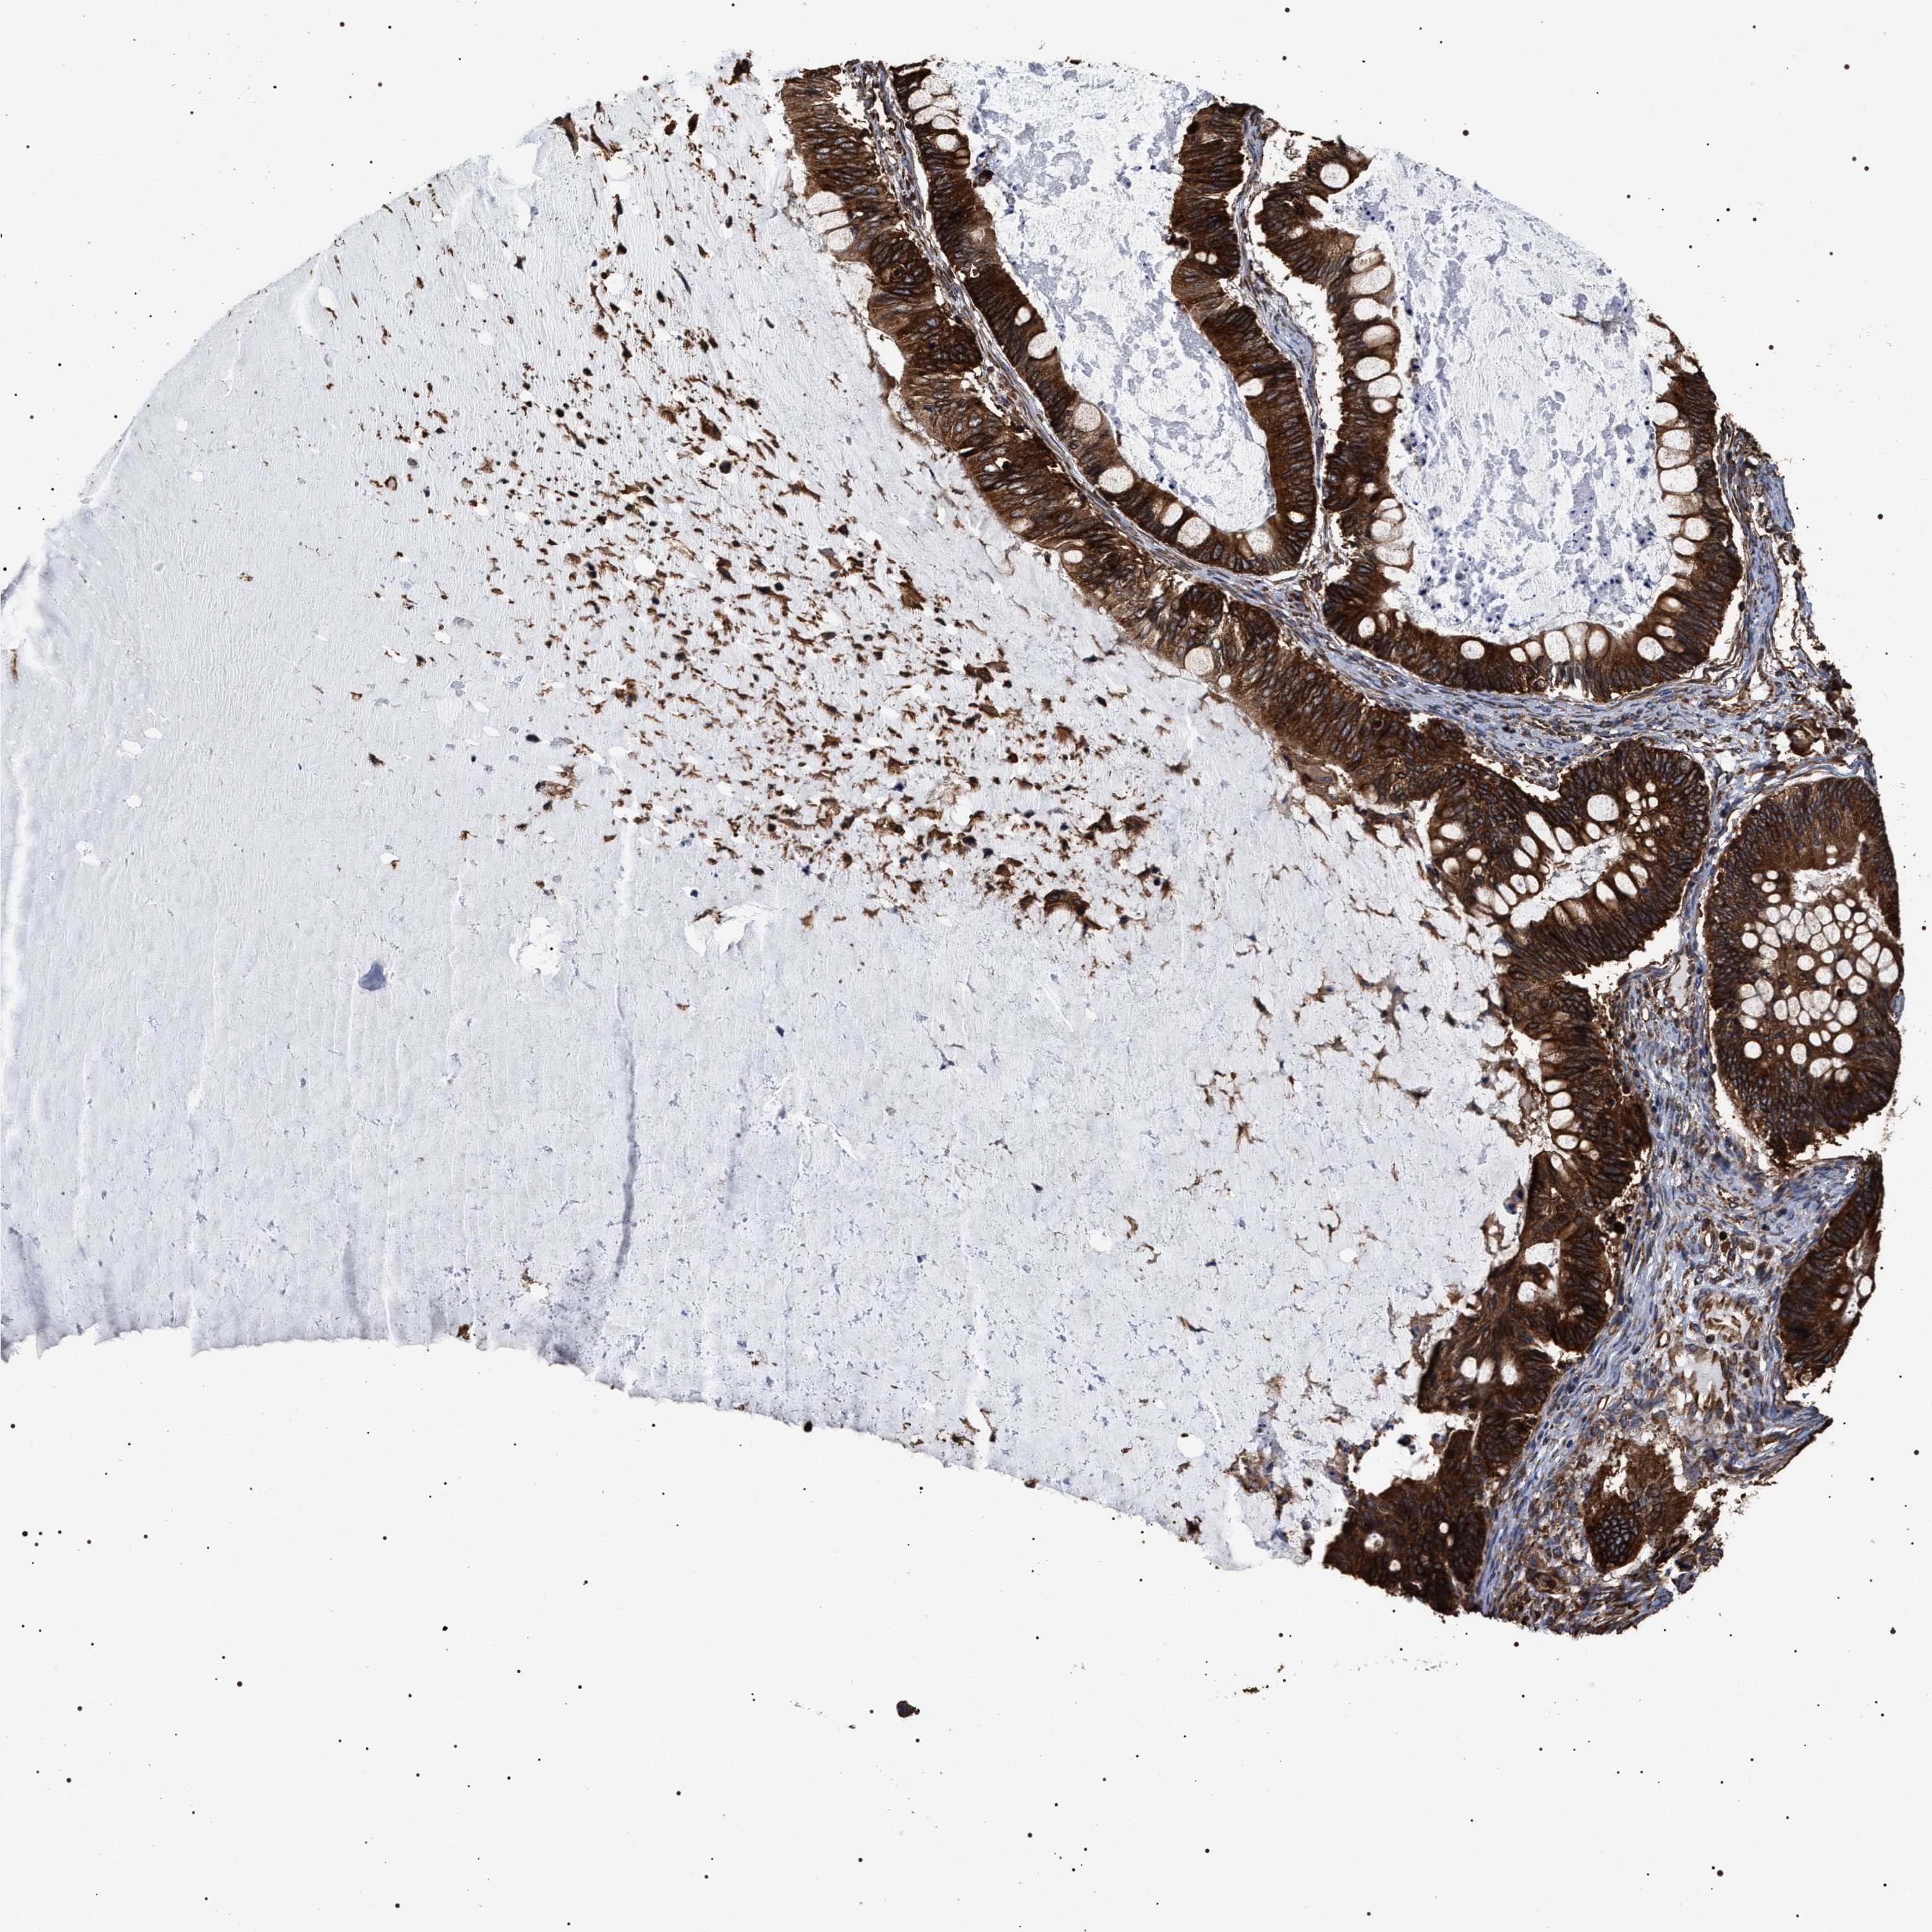

OVARIAN CANCER - Protein expressioni

A mouse-over function shows sample information and annotation data. Click on an image to view it in a full screen mode. Samples can be filtered based on level of antibody staining by selecting one or several of the following categories: high, medium, low and not detected. The assay and annotation is described here.

Note that samples used for immunohistochemistry by the Human Protein Atlas do not correspond to samples in the TCGA dataset.

Antibody stainingi

Antibody staining in the annotated cell types in the current human tissue is reported as not detected, low, medium, or high, based on conventional immunohistochemistry profiling in selected tissues. This score is based on the combination of the staining intensity and fraction of stained cells.

Each image is clickable and will lead to virtual microscopy that enables deeper exploration of all samples and also displays staining intensity scores, fraction scores and subcellular localization as well as patient and tissue information for each sample.

Antibody HPA020559

Antibody CAB026297

Cystadenocarcinoma, serous, NOS

Carcinoma, endometroid

Cystadenocarcinoma, mucinous, NOS

Carcinoma, NOS